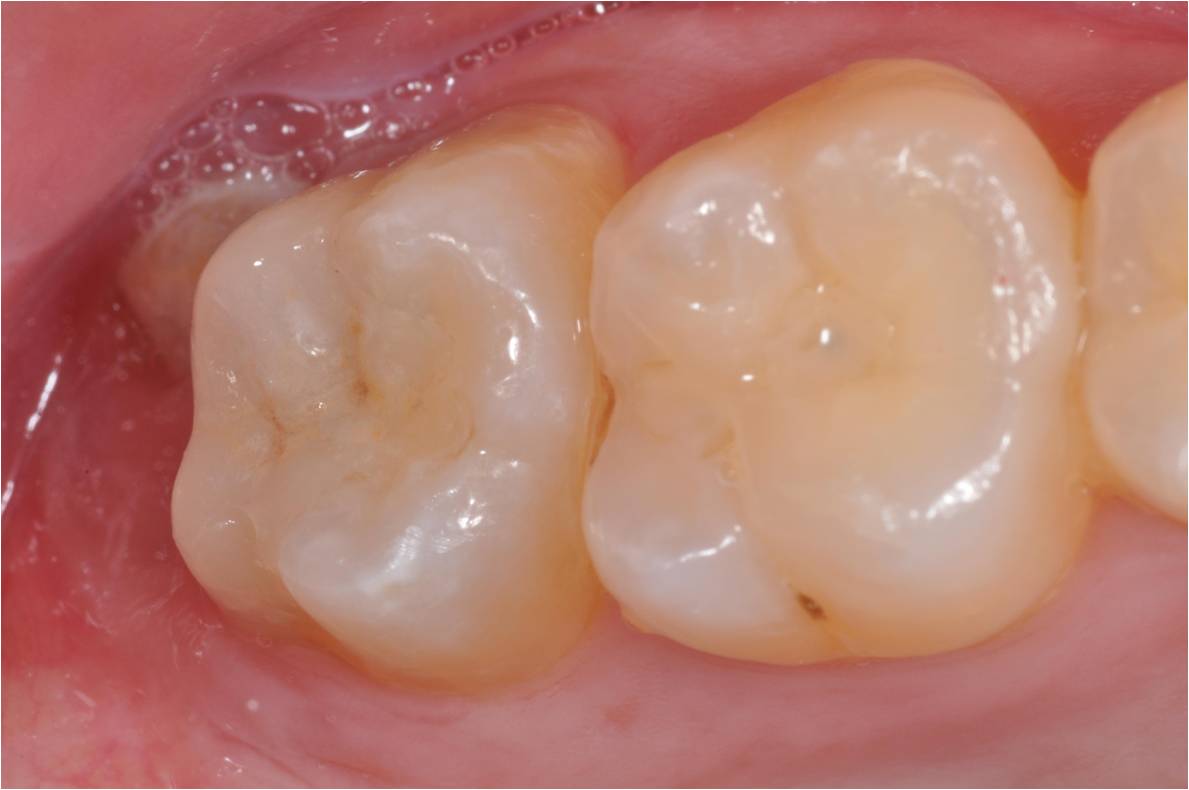

治療後,美觀與功能恢復理想

術前、術後比較